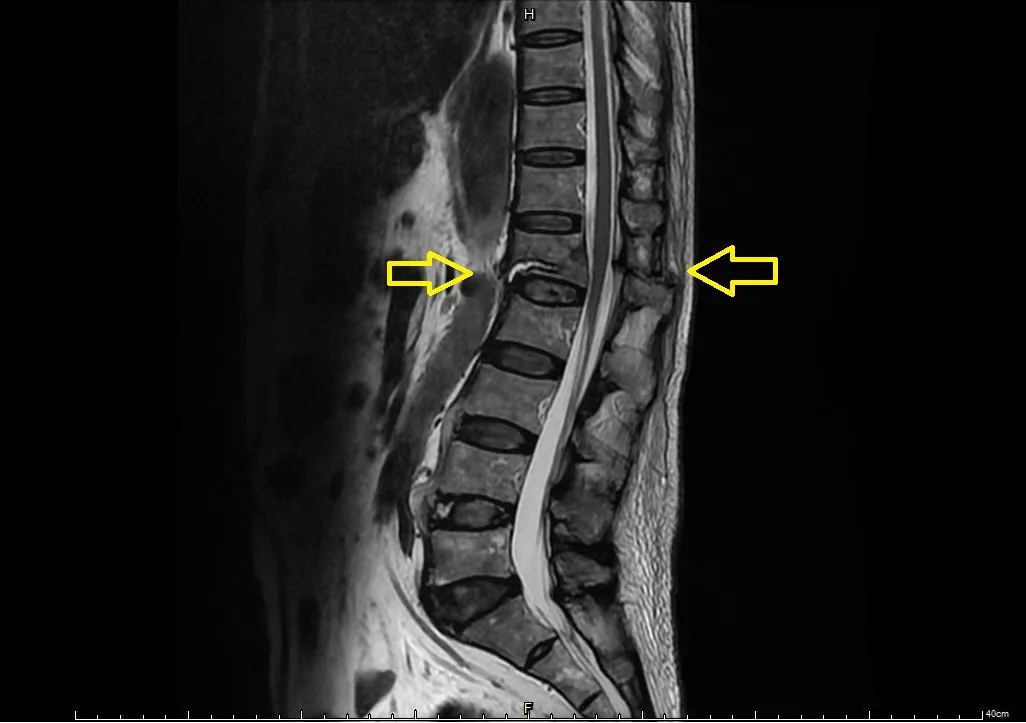

核磁共振顯示黃色箭頭處有脊椎椎體骨折以及後方脊突韌帶斷裂,位於脊髓的神經尚未有嚴重的壓迫。